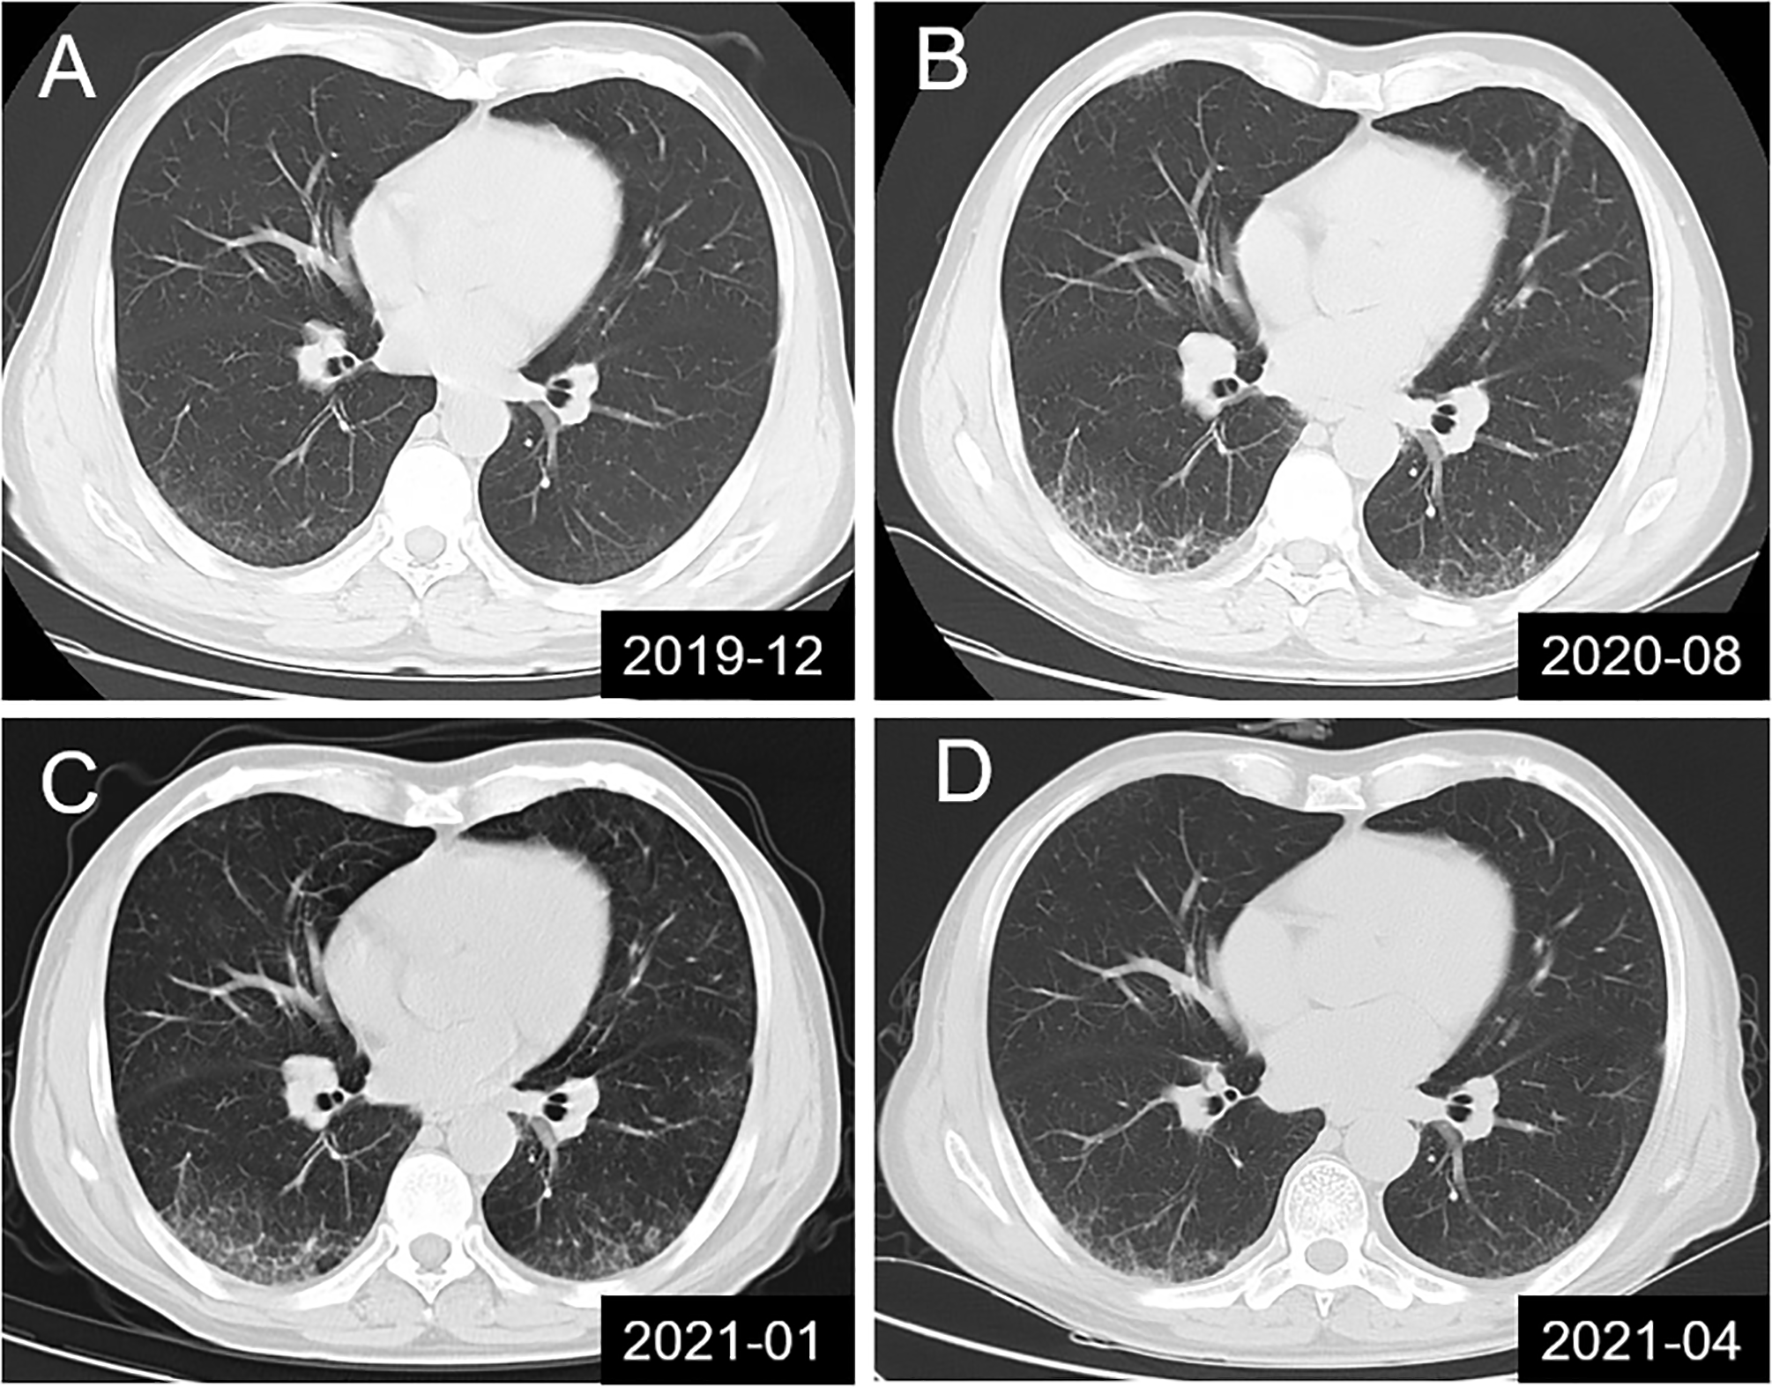

A 57-year-old man sought medical attention at our hospital after experiencing progressive limb weakness and sensory abnormalities for six weeks. The patient had developed nephrotic syndrome three years earlier. The results of his renal biopsy suggested the presence of PLA2R-associated MN and fulfilled the criteria for stage 3 MN, but immunotherapy had not yet been administered. Results of the initial physical examination at admission indicated symmetric limb weakness with Grade V- muscle strength in all four limbs; strength was impaired in both proximal and distal muscles in the upper and lower limbs, poor stability and accuracy in the finger-to-nose and heel-to-knee-to-shin test, loss of tendon reflexes, decreased proprioception, and decreased distal superficial sensation in a glove and stocking pattern. The patient required mobility aids for walking. Neuroelectrophysiological results were as follows: motor distal latency prolongation ≥50% above the upper limit of normal values (ULN) in the bilateral peroneus and right medianus; reduction of motor conduction velocity ≥30% below the lower limit of normal values (LLN) in the bilateral medianus, right musculocutaneous nerve, femoral nerve, and left peroneus; motor conduction block, ≥30% reduction of the proximal relative to distal negative peak compound muscle action potential (CMAP) amplitude in the bilateral medianus, right ulnaris, and left peroneus; sensory conduction abnormalities (prolonged distal latency or reduced sensory nerve action potential [SNAP] amplitude or slowed conduction velocity outside of normal limits) in the medianus, ulnaris, radial nerve, peroneus supers, and suralis. This was mainly manifested in the distal lower limbs (Table 1), which fulfilled the electrophysiological diagnostic criteria for CIDP developed by the Federation of European Neuroscience Societies/Peripheral Nerve Society (1). Results of the routine cerebrospinal fluid (CSF) biochemical analysis were as follows: chloride, 132.2 mmol/L; glucose, 3.00 mmol/L; protein, 1.65 g/L; and total cell count, 7/uL (nucleated cell count: 7/uL). Other biochemical test results were as follows: serum albumin, 29.8 g/L; triglycerides, 1.09 mmol/L; total cholesterol, 4.75 mmol/L; high-density lipoprotein, 1.03 mmol/L; and low-density lipoprotein, 2.85 mmol/L. The serum PLA2R antibody titer measured by ELISA was 23.75 RU/mL (negative: <14.00 RU/mL). Abnormalities were not found in the anti-NMDAR, anti-AMPAR1, anti-AMPAR2, anti-LGI1, anti-CASPR-2, and anti-GABABR antibodies in CSF. Tests for paraneoplastic antibodies (Hu, Yo, Ri, CV2/CRMP5, Ma1, Ma2, SOX1, Tr, Zic4, GAD65, PKCγ) and anti-ganglioside antibodies (GM1, GM2, GM3, GM4, GD1a, GD1b, GD2, GD3, GT1a, GT1b, GQ1b) in the serum were negative. Abnormalities were not found in complement and immunoglobulin levels and monoclonal immunoglobulins were not detected on immunofixation electrophoresis. Lung CT revealed the presence of interstitial pneumonia (Figures 1A–C show pre-treatment CT scans, Figure 1D shows the post-treatment scan). No obvious abnormalities were observed in the cervical and lumbar spine MRI results.

Figure 1 Lung CT scans showing dynamic changes in interstitial pneumonia in the studied patient. (A) Mild interstitial pneumonia found during physical examination; (B, C) Dynamic monitoring before treatment and in the absence of clinical symptoms; (D) Significant improvement in interstitial pneumonia was observed in the results of lung CT re-examination at 10 days after combination therapy with intravenous immunoglobulin, methylprednisolone and rituximab.

Through clinical manifestations, EMG results and antibody testing, the patient was diagnosed as anti-CNTN1 antibody-associated AN. Based on previous treatment experiences, the patient was administered with pulse therapy of immunoglobulin (IVIG, 0.4 g/kg) and methylprednisolone (1 g/day) for 5 days, after which the patient showed improvement in limb weakness. In view of the presence of concomitant MN, a single dose of rituximab (650 mg) was administered. The patient was able to walk without the use of mobility aids after approximately 10 days and could walk normally at the one-month follow-up. Substantial improvements were observed in interstitial pneumonia, as shown by the results of lung CT re-examination at 10 days after treatment (Figure 1D) and the results of EMG re-examination at the four-month follow-up (Table 1).

Interestingly, our patient had concomitant interstitial pneumonia in addition to CIDP with MN, which improved after the administration of immunotherapy. Studies have shown that anti-PLA2R antibodies are not merely expressed on podocytes in normal glomeruli (36) but are also present in the lungs (37) and on leukocytes (38). Further research will be required to determine if the onset of interstitial pneumonia is associated with anti-PLA2R antibodies.